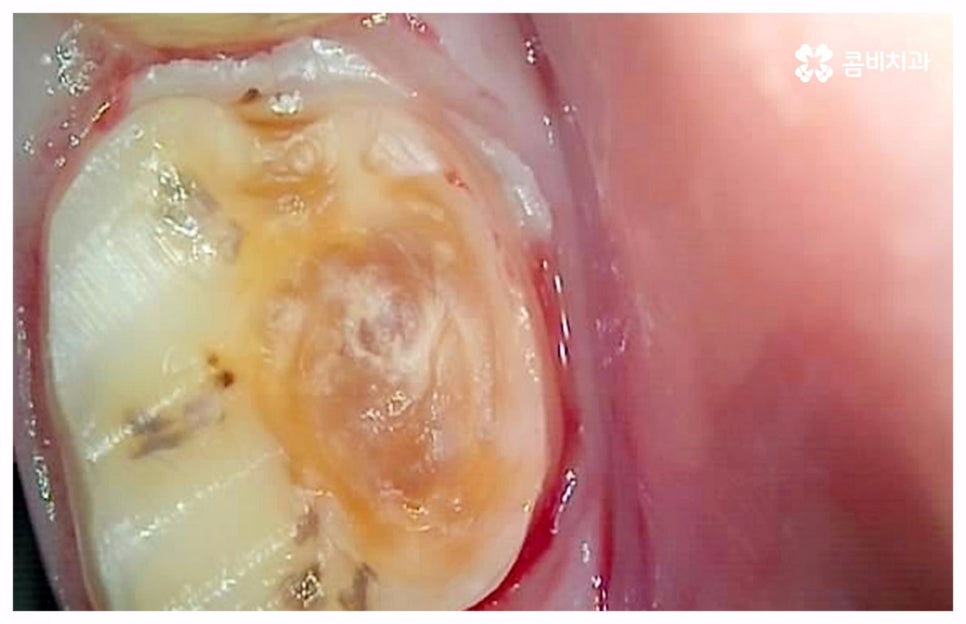

급성치수염에 대한 치료는 보통 안쪽까지 침투한 세균을 깨끗하게 긁어내고 염증 및 괴사된 치수 부분을 삭제한 다음 뿌리관(근관)을 소독하고 치과 충전물로 밀봉하는 신경 치료를 통해 이루어지는데, 이렇게 신경 치료를 진행하고 나서 후속 치료로서 남아있는 자연 치아를 보호하고 저작 기능을 제대로 수행할 수 있도록 하기 위해 주변 치아와 크기, 높이 등을 맞추어 딱 맞게 제작한 보철물을 덮어씌우는 크라운 치료를 해 주는 것이 자연 치아를 보다 오랜기간 동안 건강하게 사용할 수 있도록 하는데 크게 도움이 된다고 할 수 있어요. 경우에 따라서 앞니의 경우 신경관이 많지 않기 때문에 레진으로 치료를 마무리하는 경우도 있으니 참고해 주시면 좋을 것 같아요.

이 때 신경 치료가 끝나면 보통 통증이 사라지기 때문에 추후 시간적인 부분, 금전적인 이유 등 여러 가지 사정들로 인해서 크라운 치료가 필수적이지 않으면 신경 치료만 받고 끝마쳐도 되는지 문의를 주시는 분들이 있는데요. 크라운 치료를 해 준 치아의 경우 밀봉만 한 치아 보다 훨씬 수명이 길기 때문에 환자분들께서 크라운 치료의 필요성에 대해서 잘 인지하실 필요가 있어요. 이것은 신경 치료를 받은 치과 환자 4만 6000명을 분석한 미국 연구팀의 발표를 통해서도 알 수 있는데요. 이에 따르면 근관 속의 손상된 치수를 긁어내고 소독한 뒤 충전물로 밀봉한 치아의 경우 평균 생존 기간이 11.1년이었던 것에 반해서 추후 크라운까지 씌운 치아의 평균 수명은 약 20년으로 길어졌다고 하니 의료진과 충분히 상담하셔서 자신의 상황에 잘 맞는 보철물로 크라운 치료까지 끝마치시길 권유드리고 있습니다.